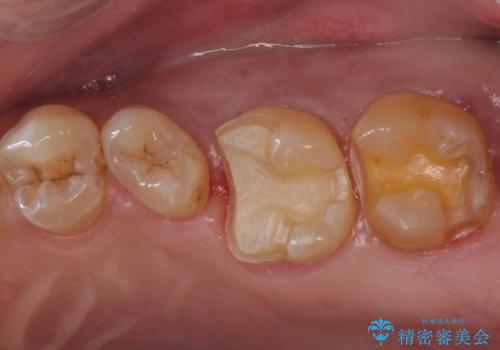

歯が欠けた

- 歯が欠けたとのことで来院された患者様です。

1本はゴールドアンレー、もう1本はセラミックインレーで修復します。